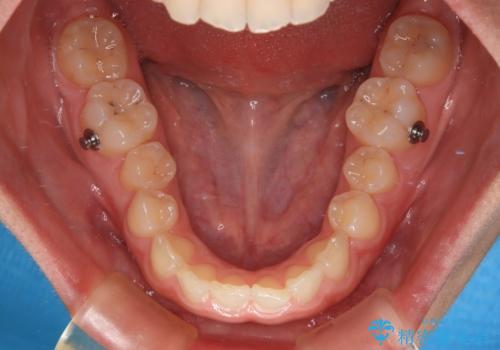

インビザライン単体でも同様の結果が得られる可能性がありますが、万が一奥歯がうまく後方移動できなかった場合、リカバリーが非常に大変となるため、事前に補助装置を併用して確実に結果が得られるように工夫をしています。